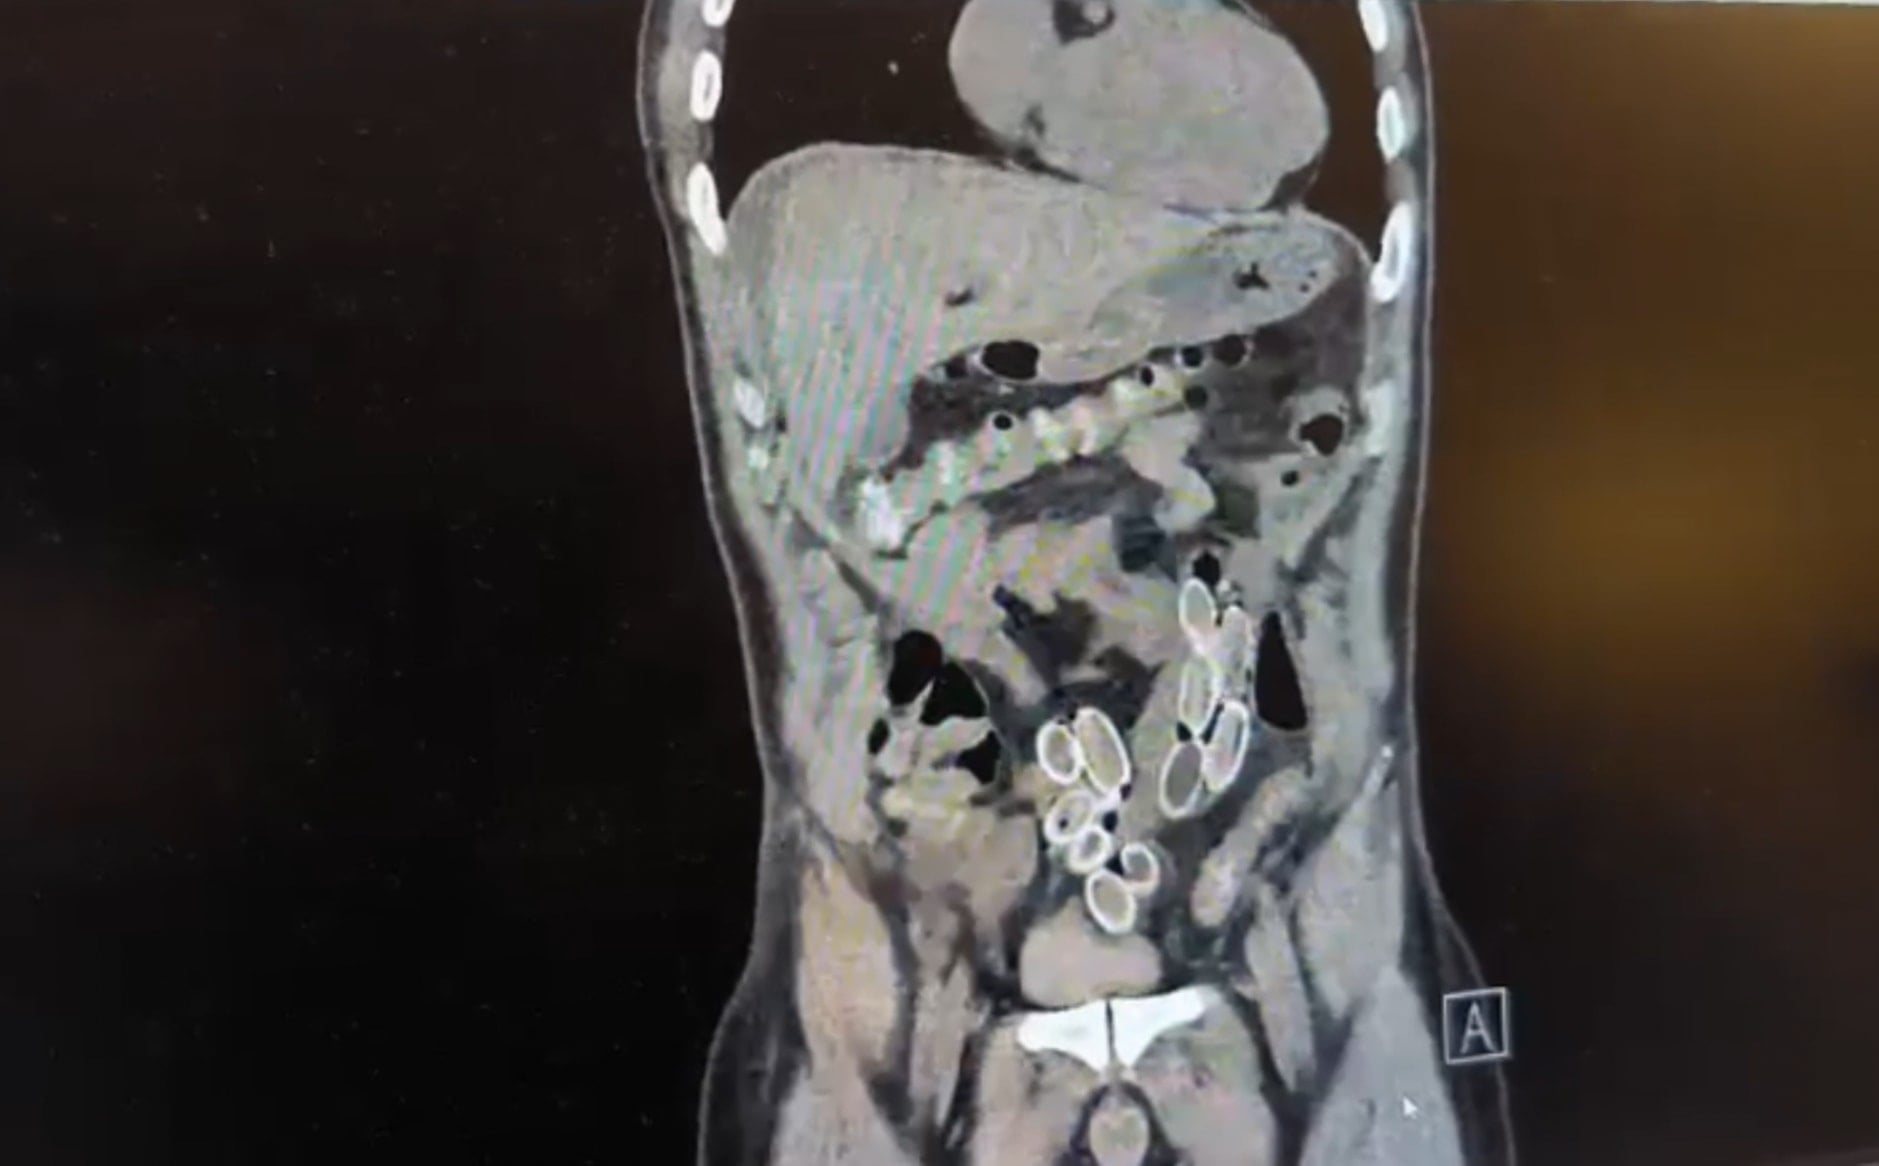

Yapılan muayenenin ardından çekilen tomografide Cüneyt Ç.’nin mide ve bağırsaklarında yabancı maddeler tespit edildi. Bunun üzerine hastane durumu polis ekiplerine bildirdi. İhbar sonrası Beşiktaş Asayiş Büro Amirliği ekipleri konuyla ilgili çalışma başlattı.

Doktorların değerlendirmesi sonrası ameliyata alınan Cüneyt Ç.’nin mide ve bağırsaklarından kapsül halinde toplam 49 adet esrar macunu çıkarıldı. Kapsüllerin toplam ağırlığının 259,7 gram olduğu öğrenildi. Şüpheliye ait bir cep telefonu da inceleme yapılmak üzere polis ekiplerine teslim edildi.